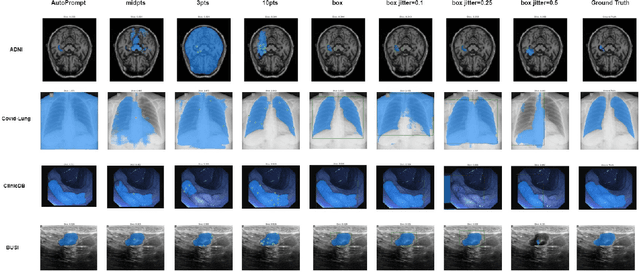

Abstract:The Segment Anything Model (SAM) made an eye-catching debut recently and inspired many researchers to explore its potential and limitation in terms of zero-shot generalization capability. As the first promptable foundation model for segmentation tasks, it was trained on a large dataset with an unprecedented number of images and annotations. This large-scale dataset and its promptable nature endow the model with strong zero-shot generalization. Although the SAM has shown competitive performance on several datasets, we still want to investigate its zero-shot generalization on medical images. As we know, the acquisition of medical image annotation usually requires a lot of effort from professional practitioners. Therefore, if there exists a foundation model that can give high-quality mask prediction simply based on a few point prompts, this model will undoubtedly become the game changer for medical image analysis. To evaluate whether SAM has the potential to become the foundation model for medical image segmentation tasks, we collected more than 12 public medical image datasets that cover various organs and modalities. We also explore what kind of prompt can lead to the best zero-shot performance with different modalities. Furthermore, we find that a pattern shows that the perturbation of the box size will significantly change the prediction accuracy. Finally, Extensive experiments show that the predicted mask quality varied a lot among different datasets. And providing proper prompts, such as bounding boxes, to the SAM will significantly increase its performance.